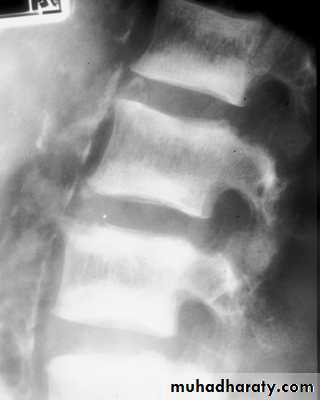

* Rugger jersey spine

Hyperparathyroidism

Xrays:sub-periosteal resorption

pepper pot skull

rugger jersey spine

cystic brown tumours